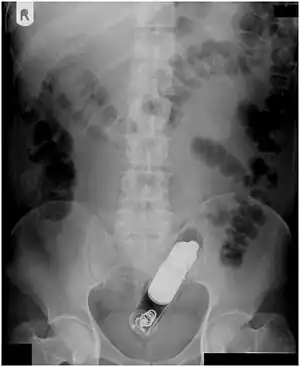

| Radiograph of a male abdomen with a vibrator inside the rectum | |